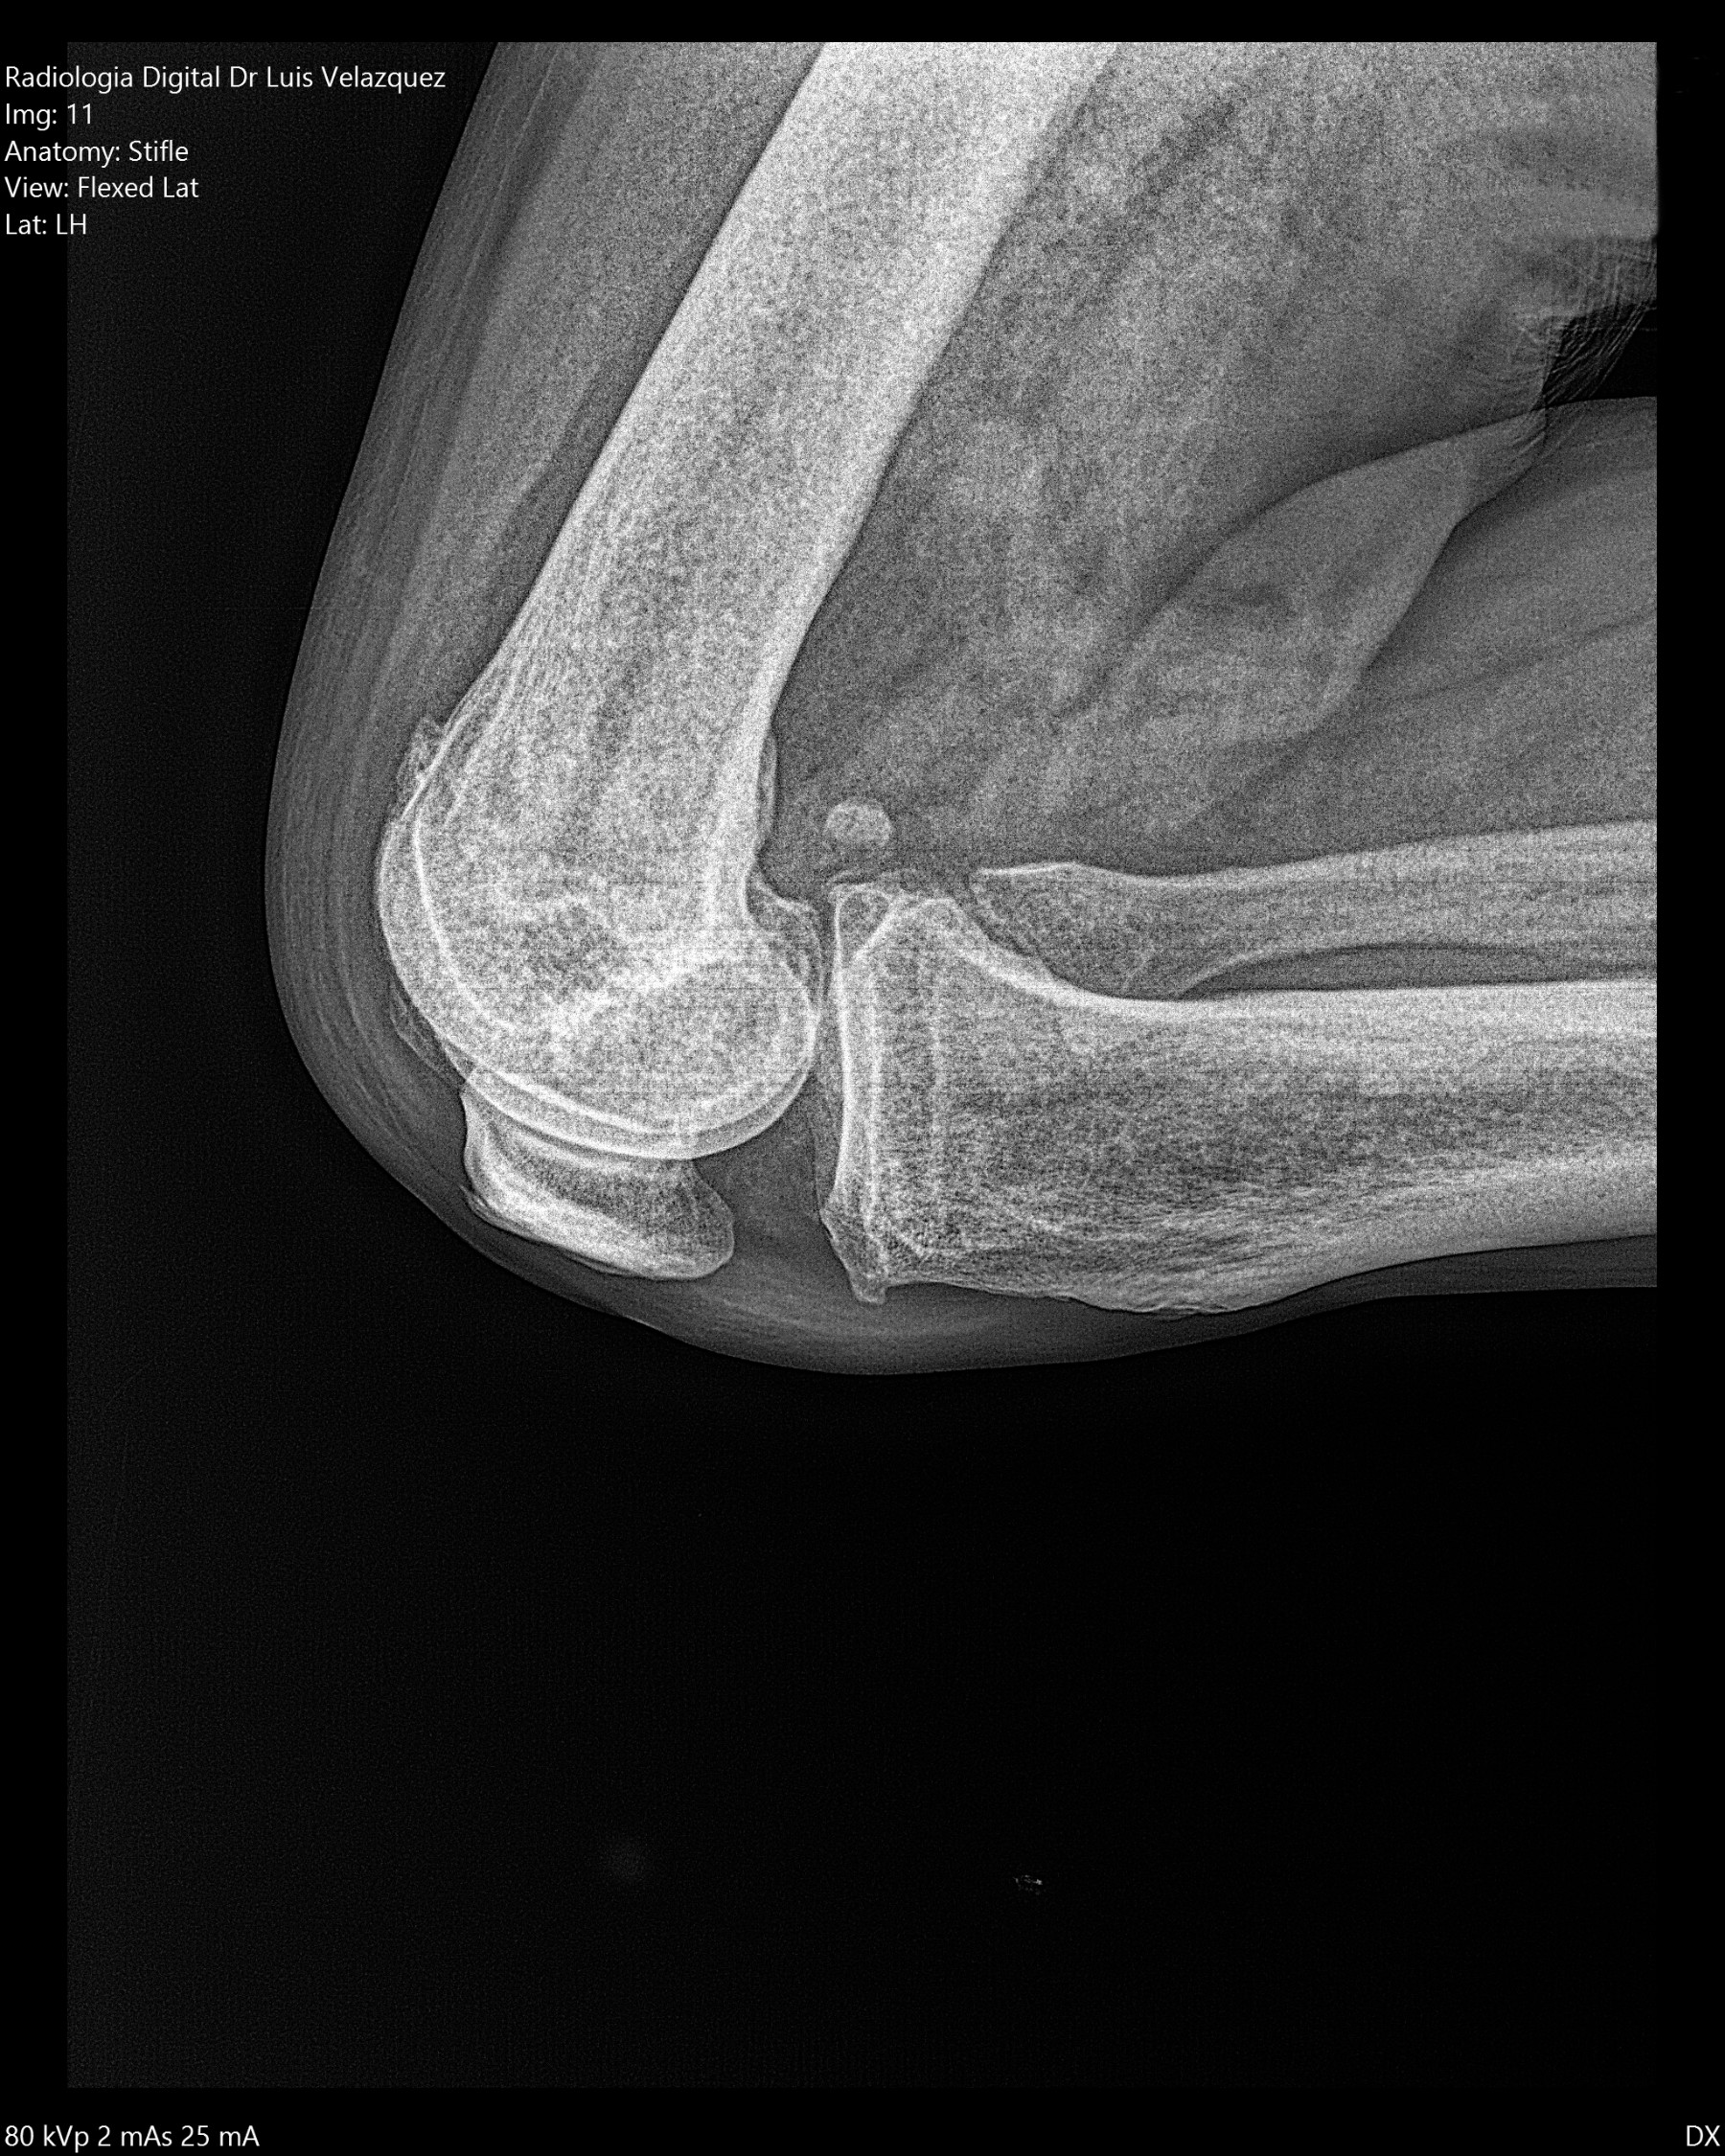

Cambios Térmicos en las Extremidades de Caballos,

Asociados a Golpes y su Evaluación por Termografía.

Los caballos de salto, en competencia, pueden derribar obstáculos y lastimarse. Si se golpean, no siempre claudican. Considerando al calor como un signo de inflamación, se evaluaron los cambios térmicos de 6 áreas de las extremidades torácicas y pelvianas de 23 caballos de salto en nivel de competencia de 1.05 a 1.60 m de altura, por medio de termografía durante 4 días de competencia (N=2208 áreas).